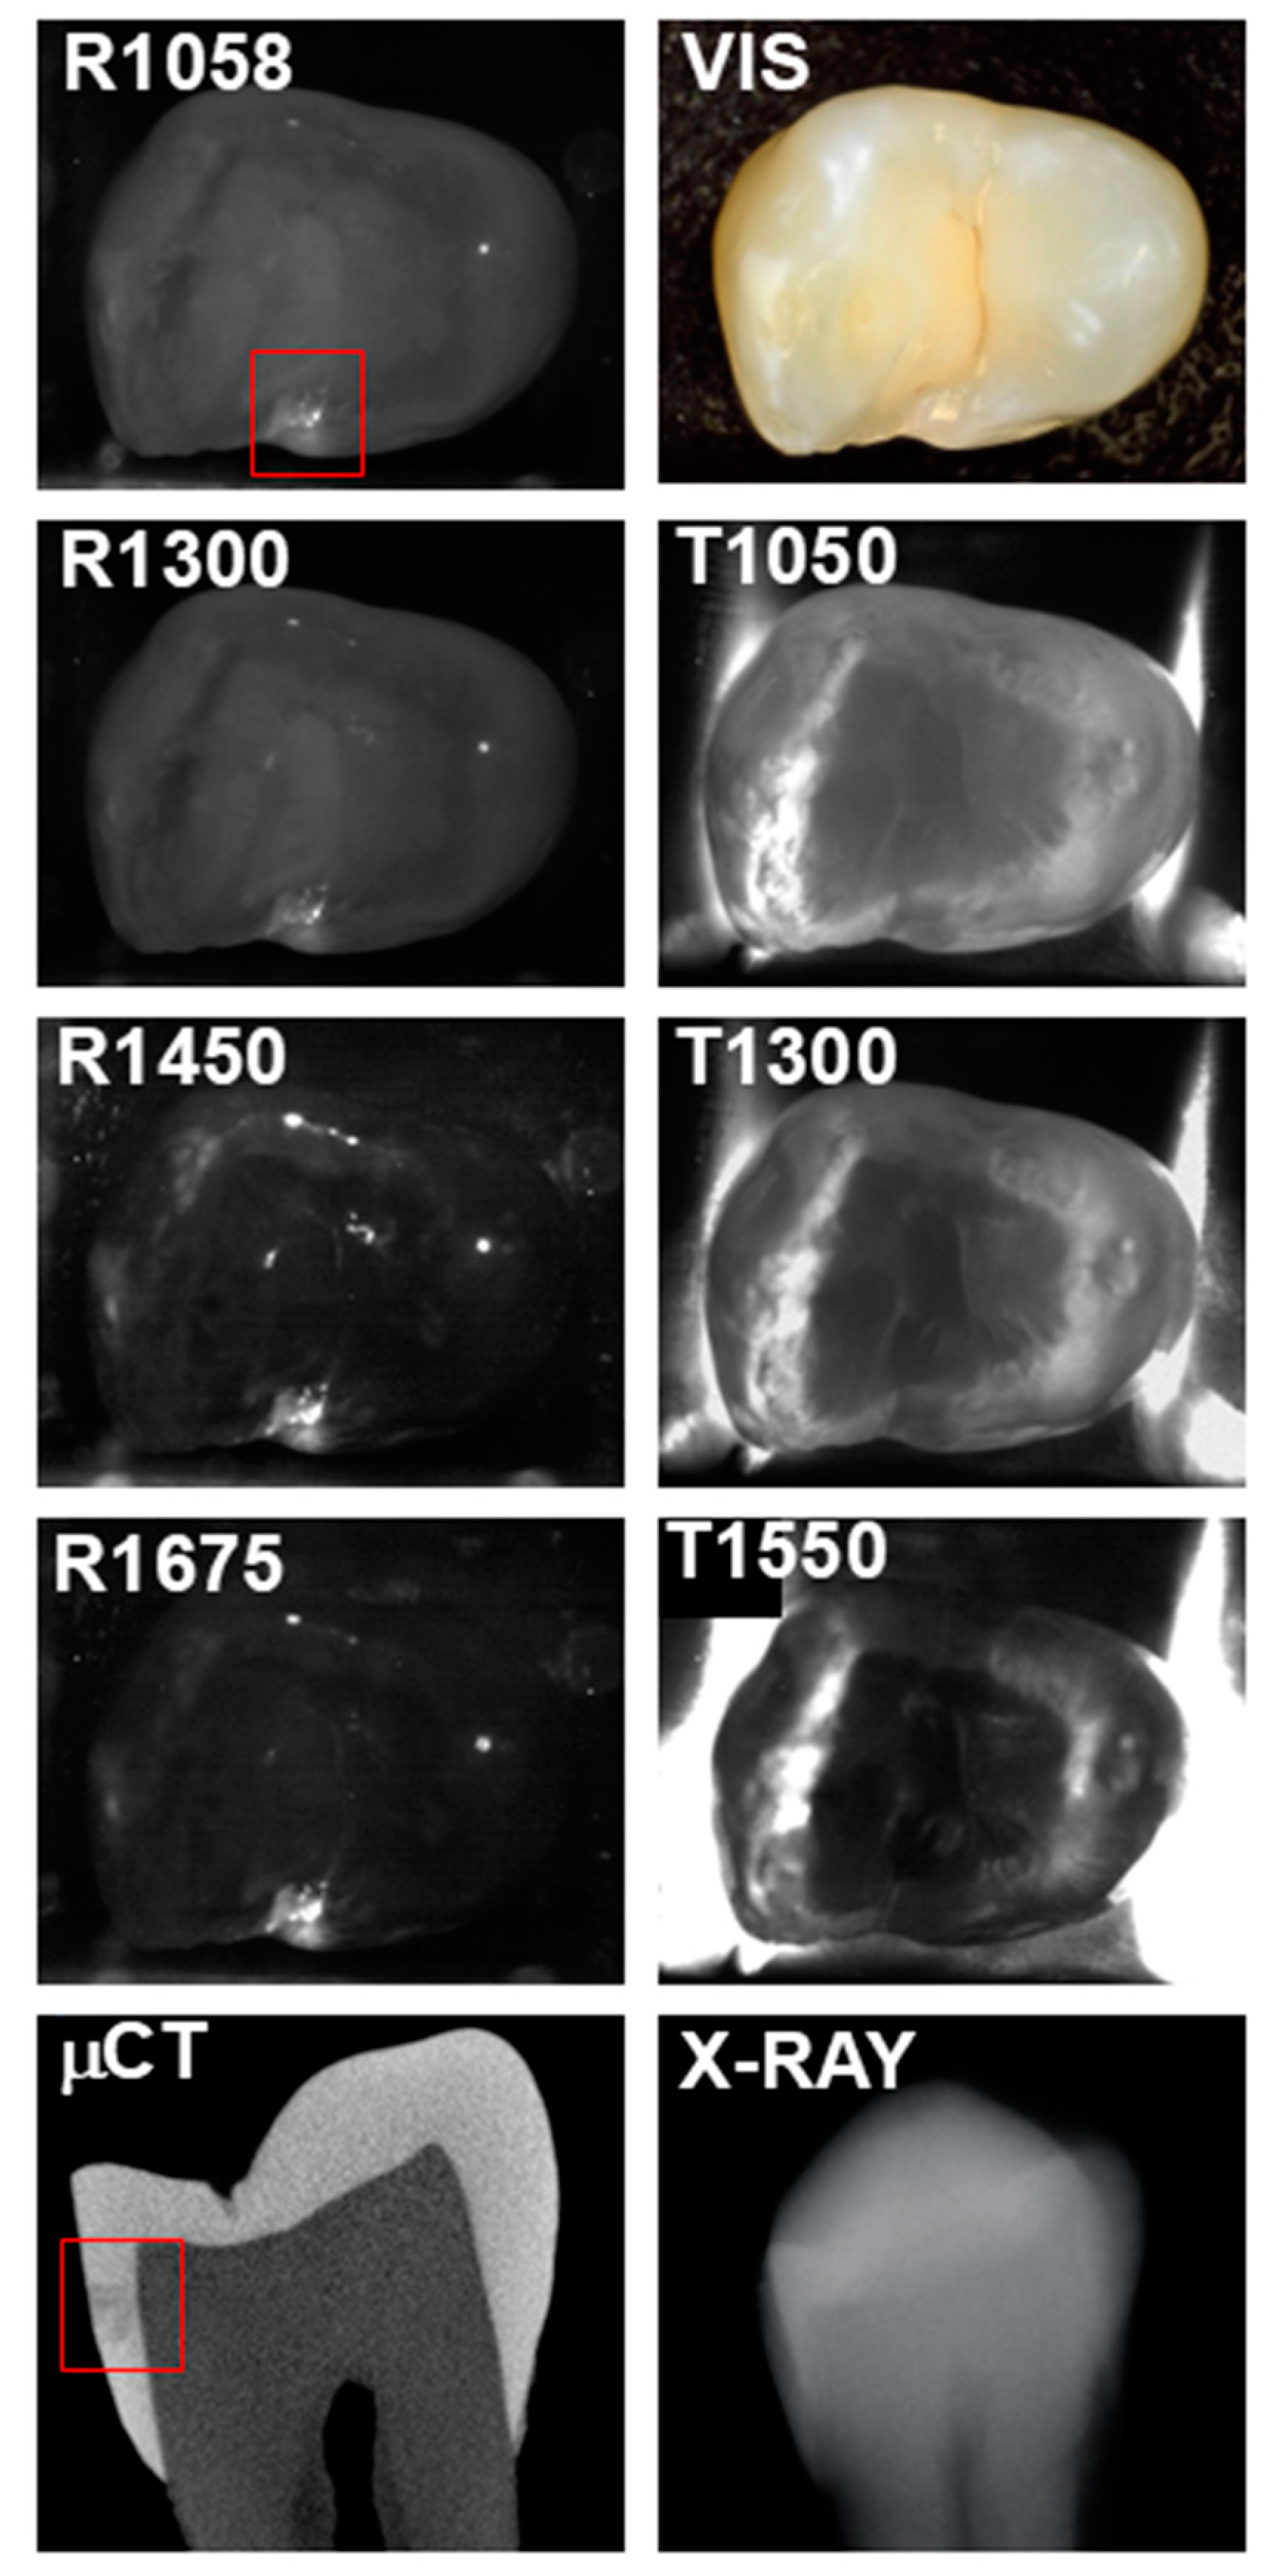

A second tooth with occlusal lesions is shown in Figure 3. The occlusal lesion area designated by the red box appears with extremely high positive contrast in all the SWIR reflectance images. The highest contrast is at 1450 nm where it is 0.95. The lesion is clearly visible with positive contrasts at 1050 and 1300 nm, and it is visible at 1550 nm; however, the occlusal lesion areas now appear with negative contrast at this wavelength for occlusal transillumination, i.e., the contrast has become inverted. A small interproximal lesion also appears in the μCT image, but it is not visible in any of the other images.

Figure 3. SWIR occlusal reflectance (R) images at 1058, 1300, 1450, and 1675 nm along with SWIR occlusal transillumination (T) images at 1050, 1300, and 1550 nm are shown for a tooth with an occlusal lesion enclosed in the red box. A color (VIS) image, a slice extracted from the μCT image and a radiograph (X-RAY) are also shown.

Reflectance at 1058 nm and 1300 nm was also included because it is also desirable to better visualize the surface of the tooth, and at longer wavelengths beyond 1400 nm the surface of sound areas of the tooth may not be visible due to the lower scattering of sound enamel and the increase in water absorption [4]. This is particularly challenging when surfaces are wet. Time-resolved SWIR reflectance imaging during the drying of lesions with forced air can be used to assess the activity of lesions [4], and it may be difficult to view the lesions to optimally position the imaging probe directly over the lesions being investigated. The use of a second reflectance wavelength may greatly aid alignment. In addition, image registration of the sequential images may benefit from the higher reflectivity, particularly at 1058 nm. The reflectance images shown in Figure 2, Figure 3 and Figure 4 clearly show the increased visibility of sound areas of the tooth compared to 1450 and 1675 nm.